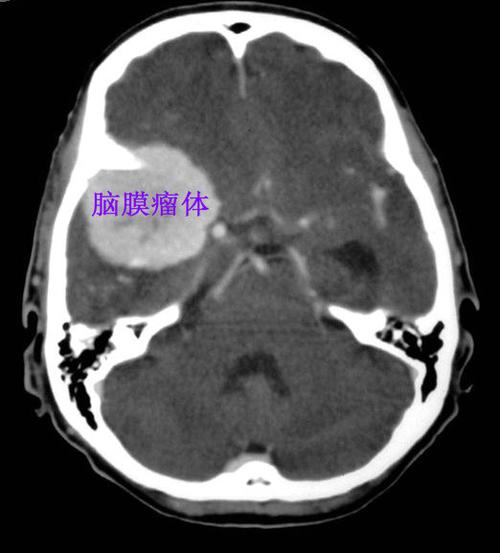

头颅ct图中显示右侧有个大大的脑膜瘤